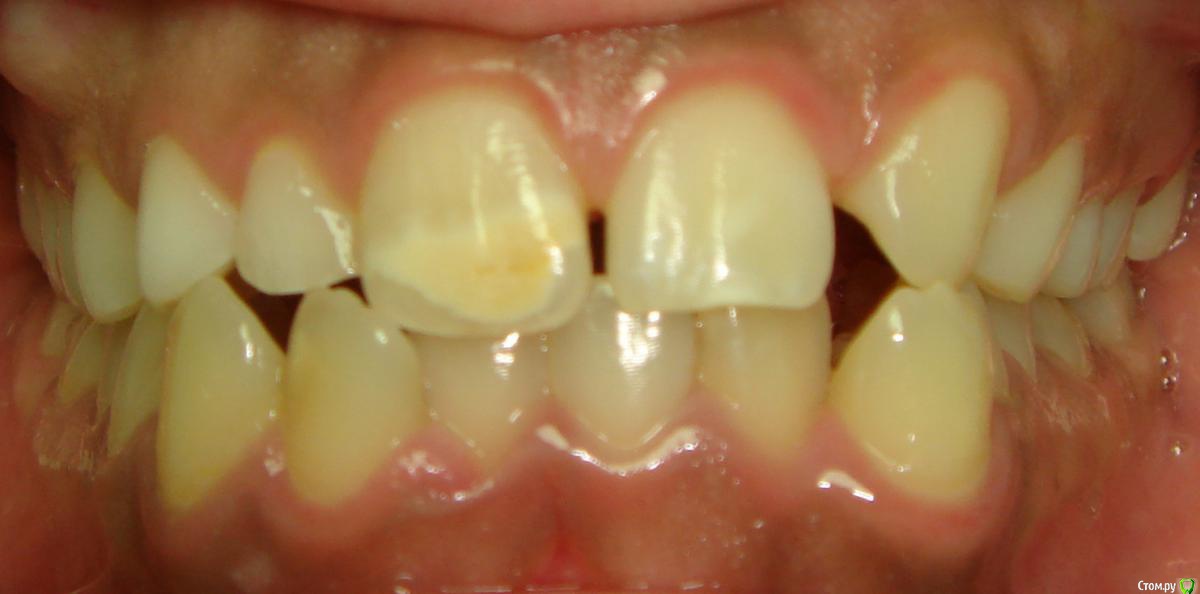

Opdihatop Опубликовано 20 февраля, 2017 Поделиться Опубликовано 20 февраля, 2017 Здравствуйте, коллеги! Вот такой вот случай третьего класса, вертикального роста, множественной первичной адентии и преинтереснейшего 13-го зуба. Девочке 14 лет. Сразу скажу, что вопреки некоторым классикам удалять клык или премоляры мы не будем, будем ставить в дугу, причем на его законное место. Может у кого-то были подобные случаи, поделитесь опытом, будьте добры. Какой план лечения и какая биомеханика тут будут самыми оптимальными? Заранее всем спасибо! Ссылка на комментарий

Opdihatop Опубликовано 20 февраля, 2017 Автор Поделиться Опубликовано 20 февраля, 2017 52, 53 молочные. 12, 22 - адентия. Клык пойдет на место 13. Когда-то на курсе Рафаэля Спены видел подобное, но, к сожалению не зафиксировал на фото. В общем и целом принцип помню. Но тут есть одно огромное НО... 14, 15 началась резорбция верхушек из-за 13 зуба, что видно по КТ. Ссылка на комментарий